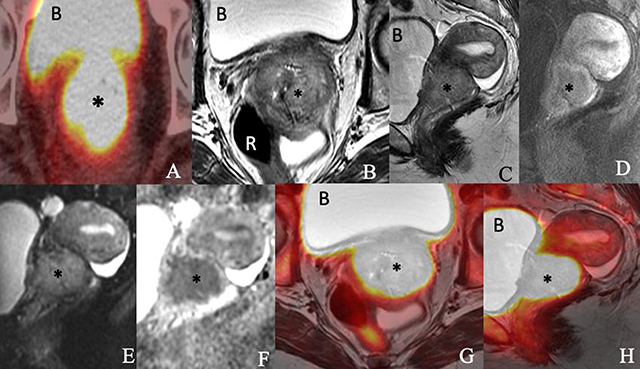

Images of a 76-year-old woman with newly diagnosed squamous cell carcinoma of the cervix consisting of an (A) axial PET/CT, (B) axial T2-weighted, (C) sagittal T2-weighted, (D) sagittal postcontrast T1-weighted, (E) sagittal diffusion-weighted (F) sagittal apparent diffusion coefficient map of MRI, (G) axial T2-weighted PET/MRI and (H) sagittal T2-weighted PET/MRI images show a 5.4 × 4.6 × 4.1-cm enhancing FDG-avid cervical mass (*) invading the parametrium and extending into the vaginal fornices and lower uterine segment. The mass exhibits restricted diffusion. The bladder (B) and rectum (R) appear to be uninvolved.